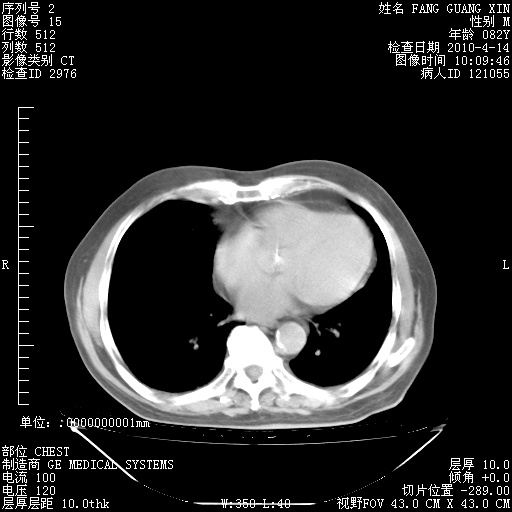

4月28日肺部CT——再次出现类似去年5月9日——透光度降低,(影像科认为)“间质性”改变。

4月28日肺部CT——再次出现类似去年5月9日——透光度降低,“间质性”改变。